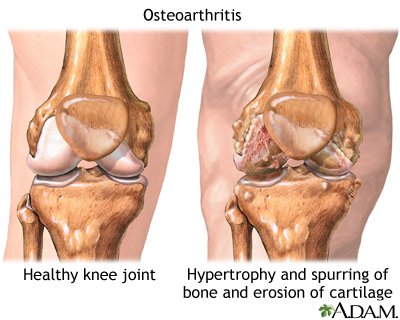

Cartilage is the firm, rubbery tissue that cushions your bones at the joints. It allows bones to glide over one another when the joint moves. When the cartilage breaks down and wears away, the fragments of the cartilage or the bones rub together. This often causes the pain, swelling, and stiffness of OA.

As OA worsens, bony spurs or extra bone may form around the joint. The ligaments and muscles around the joint may become weaker and stiffer.